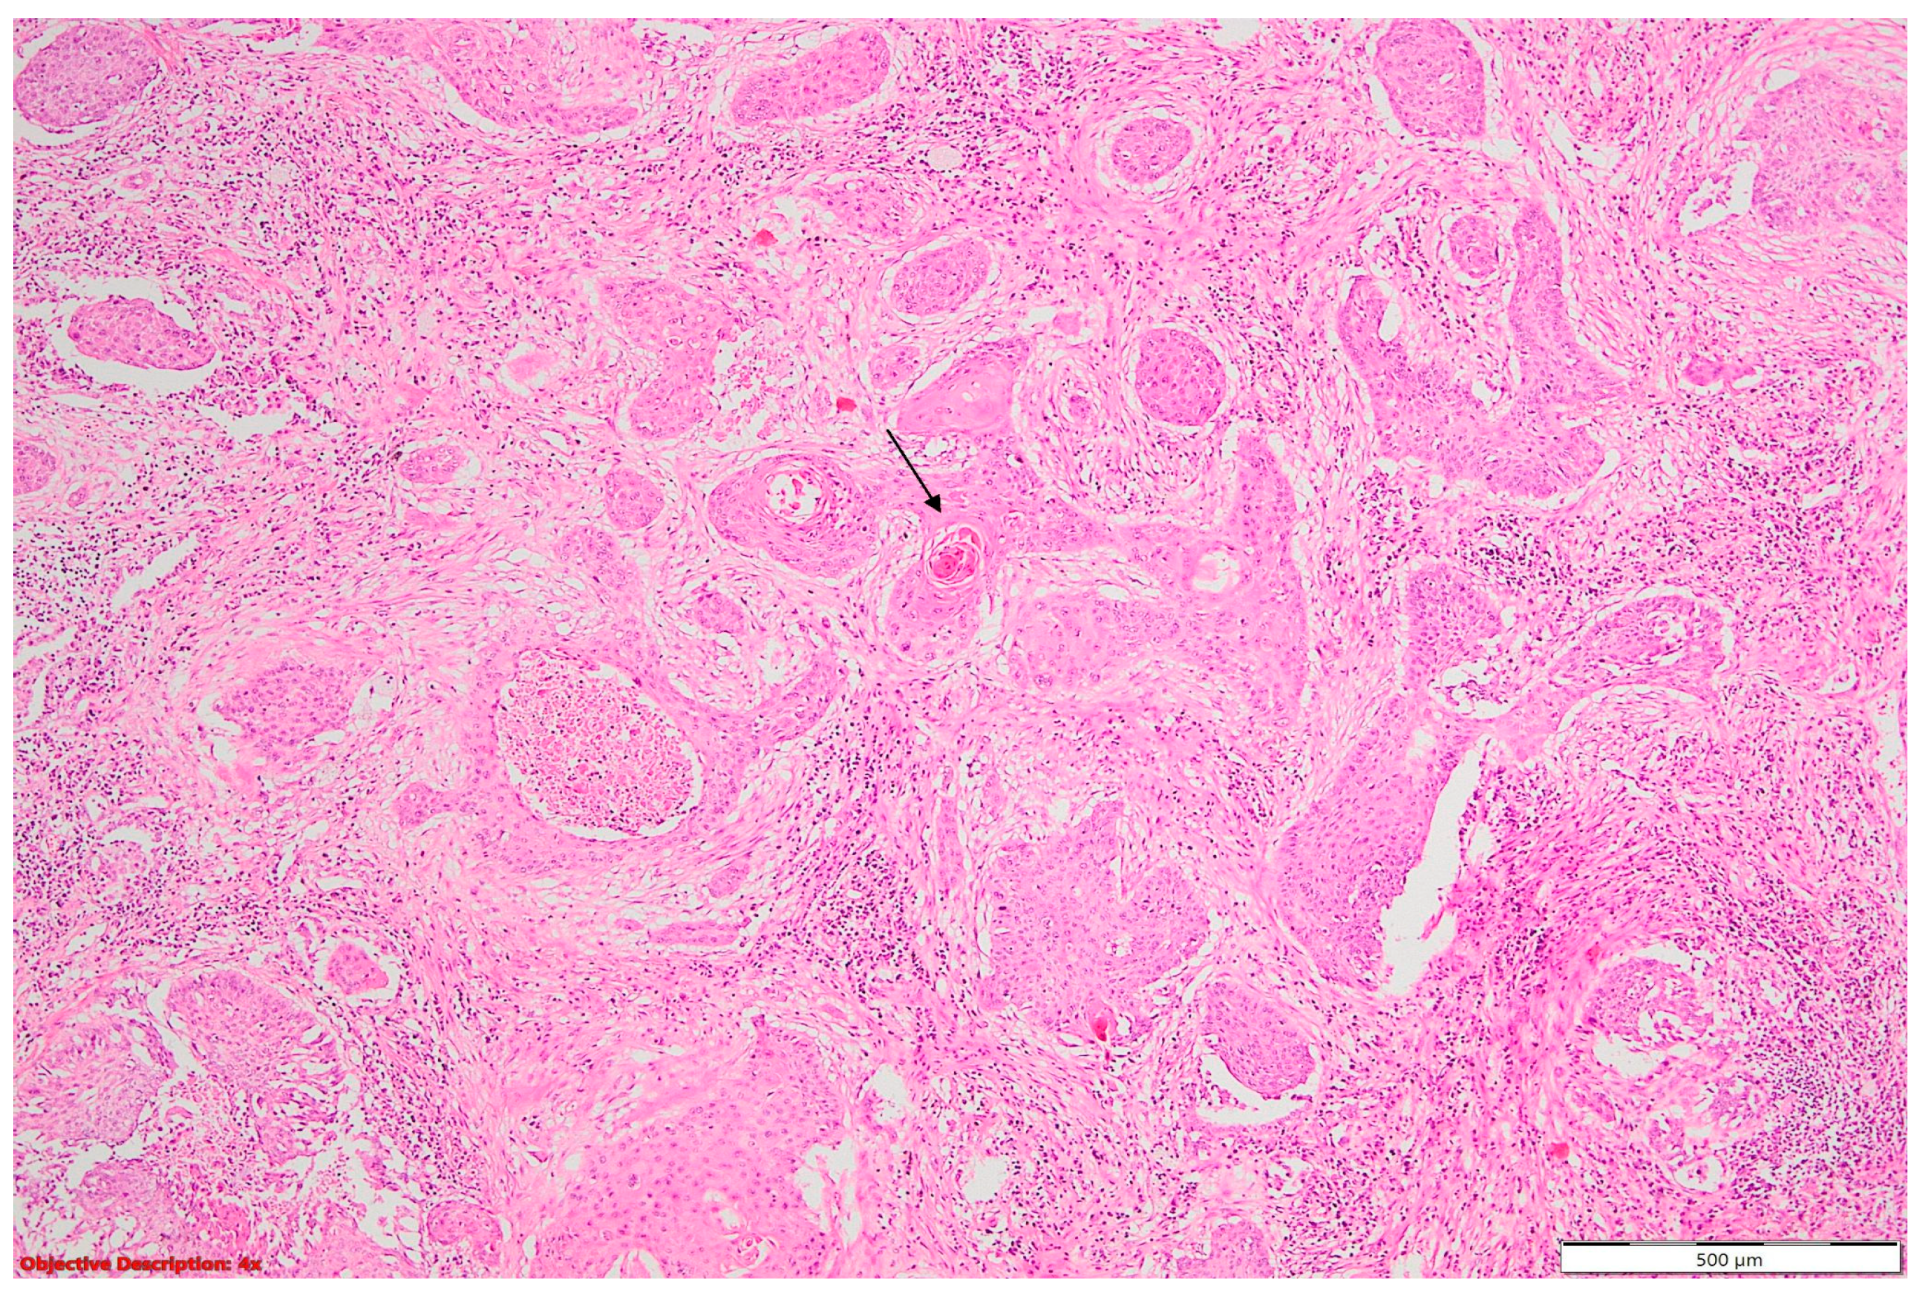

Figure 7. Lung squamous cell carcinoma (large polygonal cells with infiltrative pattern of growth; keratinization is evident →); HE, 40×.

Two of the specimens with fibronodular lesions were associated with multiple NSCLC tumors of different histopathological subtypes: one case presented with adenocarcinoma (one tumor—Figure 6) and a squamous cell tumor (one tumor—Figure 7) and another case presented with adenocarcinoma (one tumor) and large-cell neuroendocrine tumors (two tumors—Figure 8).